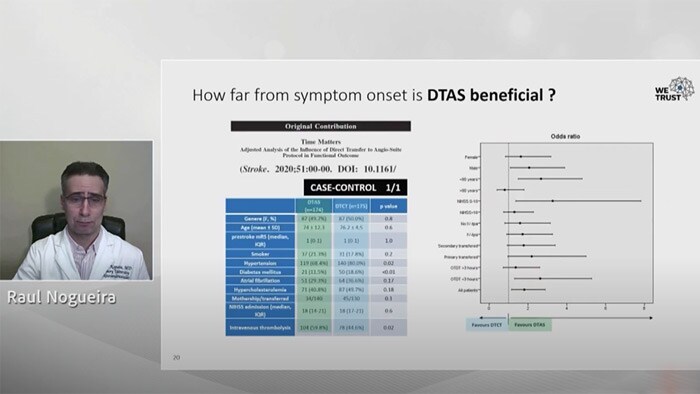

Dr Raul Nogueira (Grady Memorial Hospital, Atlanta) and Dr Marc Ribó (Hospital Val d’Hebron, Barcelona) at the SLICE Worldwide 2020 virtual event

‘Significant advances in technology mean that we are now able to identify, plan and treat ischemic stroke patients in the angiography suite, without the need for a separate CT or MR scan.’

Dr Raul Nogueira (Grady Memorial Hospital, Atlanta), LINNC 2019

1 Mendez B. et al. 2018. Direct Transfer to Angio-Suite to Reduce Workflow Times and Increase Favorable Clinical Outcome. DOI: 10.1161/STROKEAHA.118.021989 2 Saver J et al., 2016 Sep 27;316(12):1279-88. doi: 10.1001/jama.2016.13647. 3 Jadhav AP, et al. Stroke. 2017;48:1884-1889